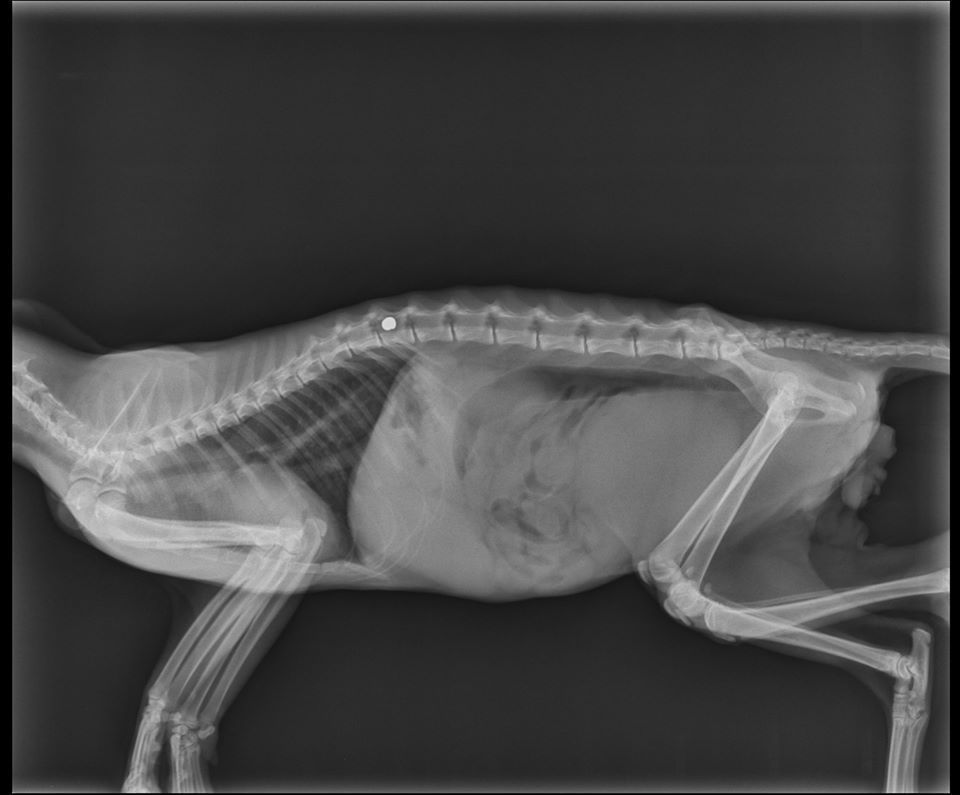

Η γατούλα της Μυτιλήνης που χειρουργήθηκε είναι καλύτερα;